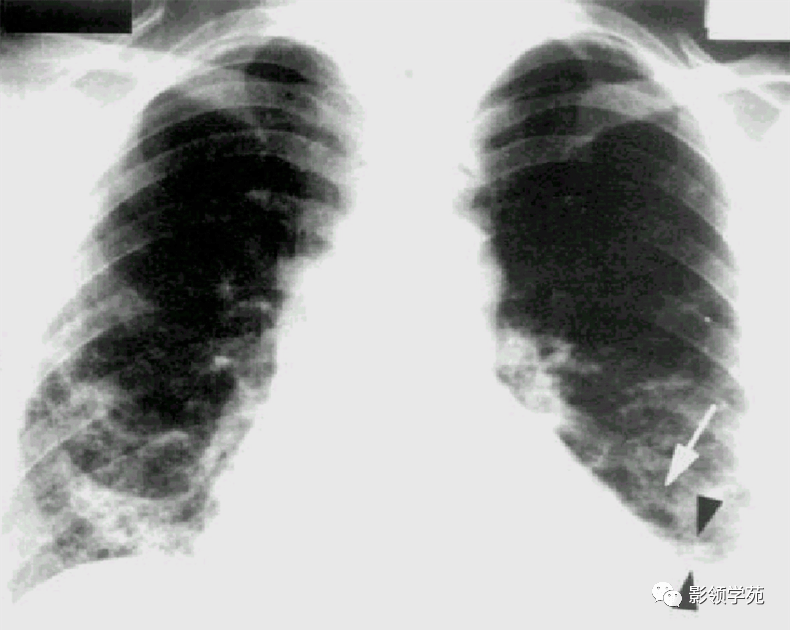

体检查出“肺结节”怎么办?如果有这些特征,很可能是肺癌来临肺结节是指在肺部发现的一个小的、局部增生的病变。许多人在体检中偶尔发现肺结节后会感到担忧,尤其是在不了解病理机制的情况下。肺结... 肺结节的大小、形状、边缘、密度等特征是判断是否恶性的关键。一般来说,如果结节较大( 3cm)、边缘不规则、密度较高、出现钙化或分叶状...